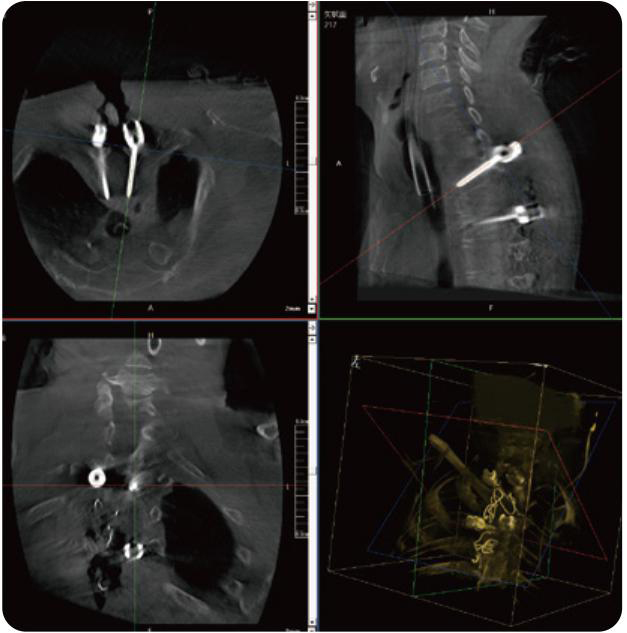

PL300B可應用于多節(jié)段脊柱外科手術,輔助醫(yī)生定位病灶部位,為脊柱外科手術(經(jīng)皮椎體成形術、椎弓根螺釘內固定術等術式)提供術前手術流程規(guī)劃、入釘位置、角度可視化引導,模擬仿真入釘輔助。

PL300B搭配普愛醫(yī)療自主研發(fā)生產(chǎn)的平板3D C形臂,借助一體化自適應配準( 軌跡配準)技術,通過追蹤C形臂三維采集軌跡,自動完成圖像坐標建立和系統(tǒng)坐標配準。配準精度更高,操作步驟少,系統(tǒng)運作效率高。